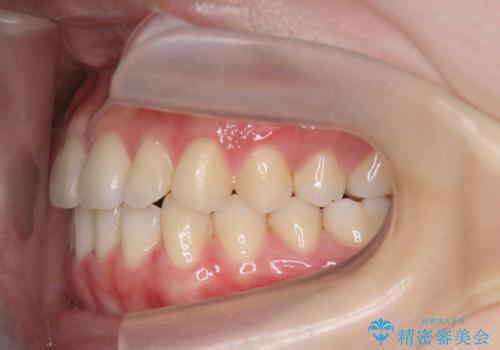

マウスピース矯正で前歯のガタつきを改善

- 上下の前歯のガタつきの改善を求めて、矯正治療を希望され来院されました。

矯正検査の結果、マウスピース矯正システム インビザラインの適応であることからワイヤーを用いず矯正治療を進めることとしました。

1日20時間以上の使用時間をきっちりと守っていただけたため、良好な治療結果、歯並びを手に入れることができました。